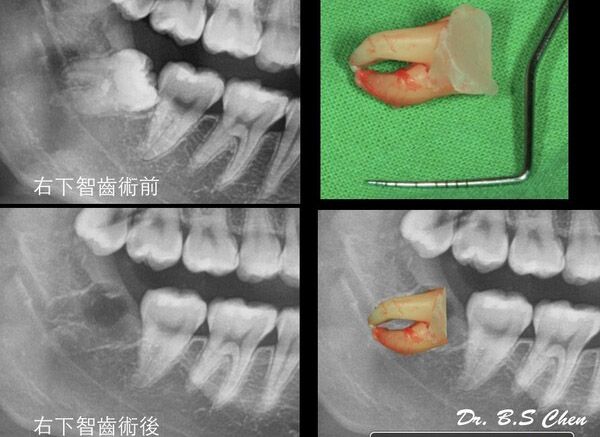

微創智齒手術案例分享

成效因人而異,必須跟從專業醫師指引

案例照片與內容均取得當事人授權同意使用,請勿私自轉載與分享